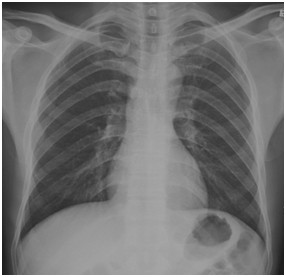

临床助理医师实践技能考试模拟试题:“ X线-正常胸片 ”影像诊断!

2022-03-29

2022年临床助理医师实践技能考试影像诊断模拟题(2分)

临床助理执业医师实践技能考试第一站例题:影像诊断